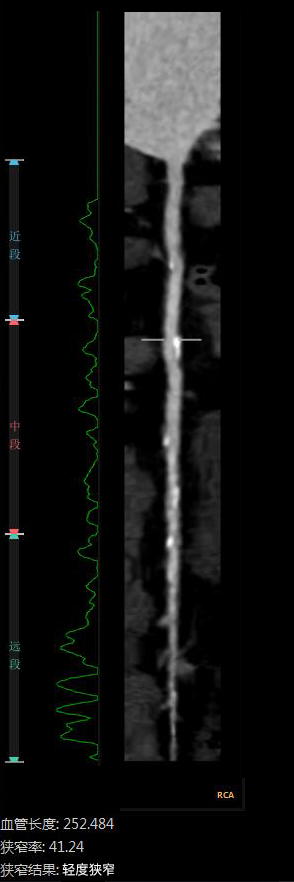

“CTA冠脈全自動(dòng)診斷”

Automatic Coronary Diagnosis

全自動(dòng)圖像重建/分割

全自動(dòng)量化測量

云端AI的CTA冠狀動(dòng)脈全自動(dòng)診斷

重構了CTA冠脈檢查的極簡(jiǎn)流程

數十倍地提升了工作效率

診斷質(zhì)量得到AI賦能

變得更加穩定、優(yōu)質(zhì)